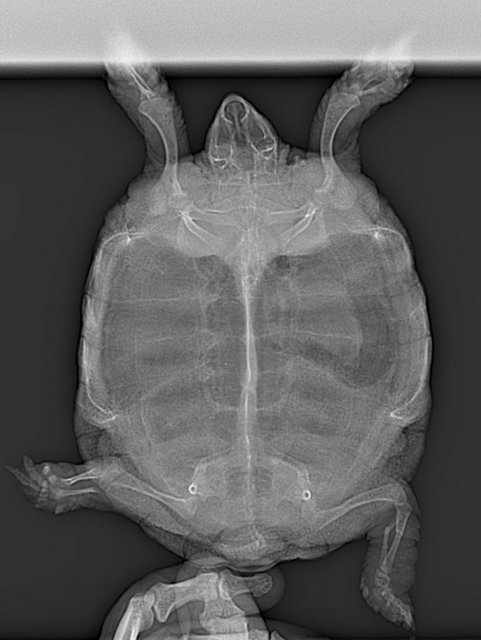

Предыстория такова,три месяца назад чепа умудрилась отодвинуть дверцу тера и естественно выпала на пол (50 см. высота).Сломала заднюю лапу.

Поехали у Эскину,сказал "давайте попробуем без вмешательств",окей - давайте.Месяц Дуська сидела,не шевелилась,заживляла лапу,через месяц поехали на рентген,Филипп сказал что появилась костная мозоль,заживает и мол через месяц всё должно прийти в норму.

Прошло два месяца,но чепка продолжала волочить лапку,да и болталась она как то неестественно.Врач был в отпуске ,я волновался,поехали в ближайшую ветеринарку,просто сделать рентген.Рентген показал что кости не срослись.

Снимки рентгена прикрепляю,первый "с мозолью"(два месяца назад)  ,второй свежий,вчерашний.

Дуся перелом Рентген 25.04.2024г..jpg

ЭКЗОТИКА_ДУСЯ_Тело целиком-ДВ_170310[1].jpg